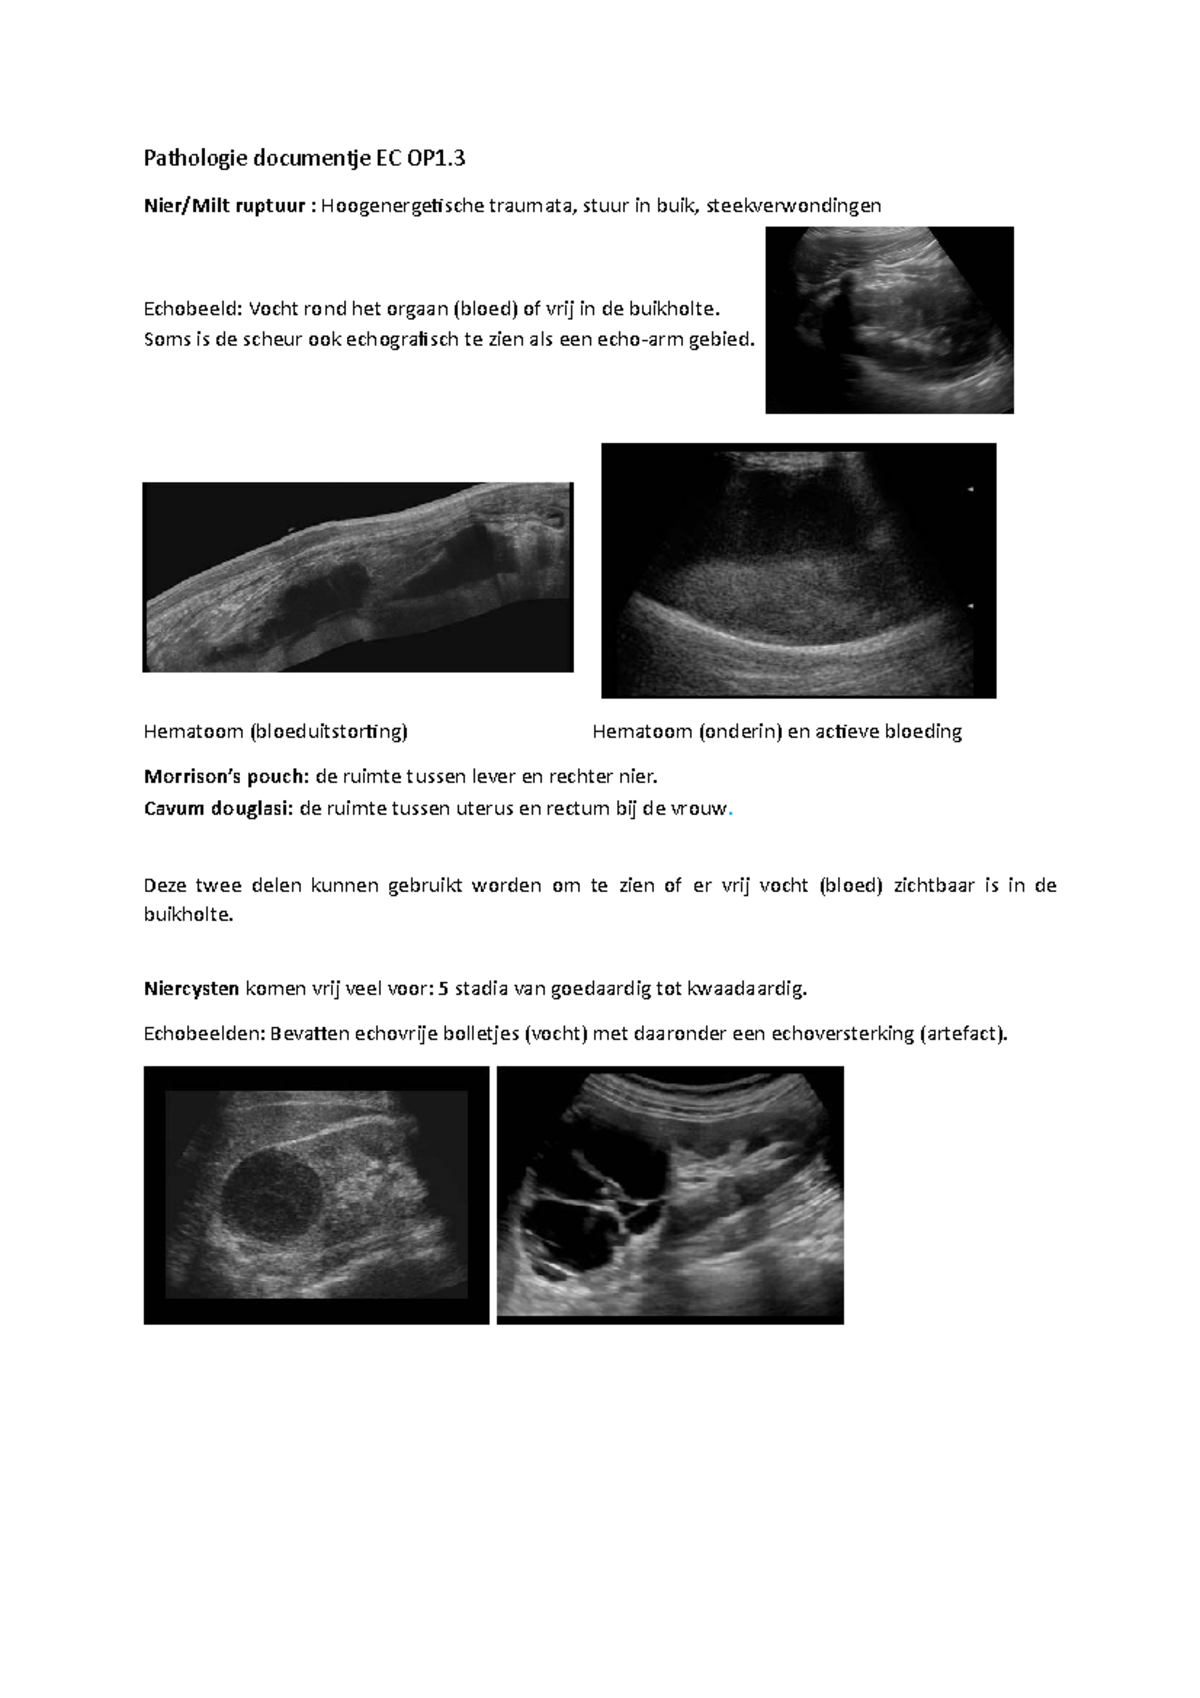

EC OP1.3 Echo Pathologie Pathologie documentje EC OP1. Nier/Milt ruptuur Hoogenergetische